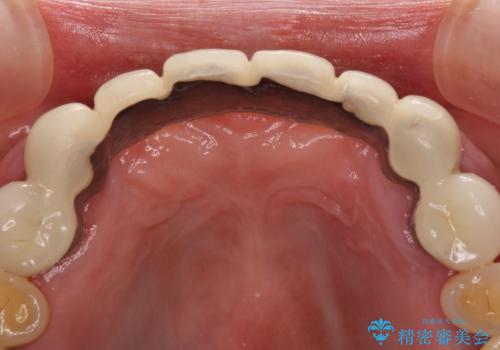

また、前歯のブリッジへの咬合力の負担が大きく、土台となっている歯が揺れてしまっていたため、インプラント埋入により奥歯への負担を軽減することとしました。

歯周外科処置を行ったことで歯周ポケットはなくなり、毎回のブラッシングの度に嫌な思いをしていた出血は認められなくなりました。

上下前歯の見え方を気にされており、歯だけをみると大変長くなりましたが、笑ったときの口元は自然な外見となり、患者様には大変満足していただきました。